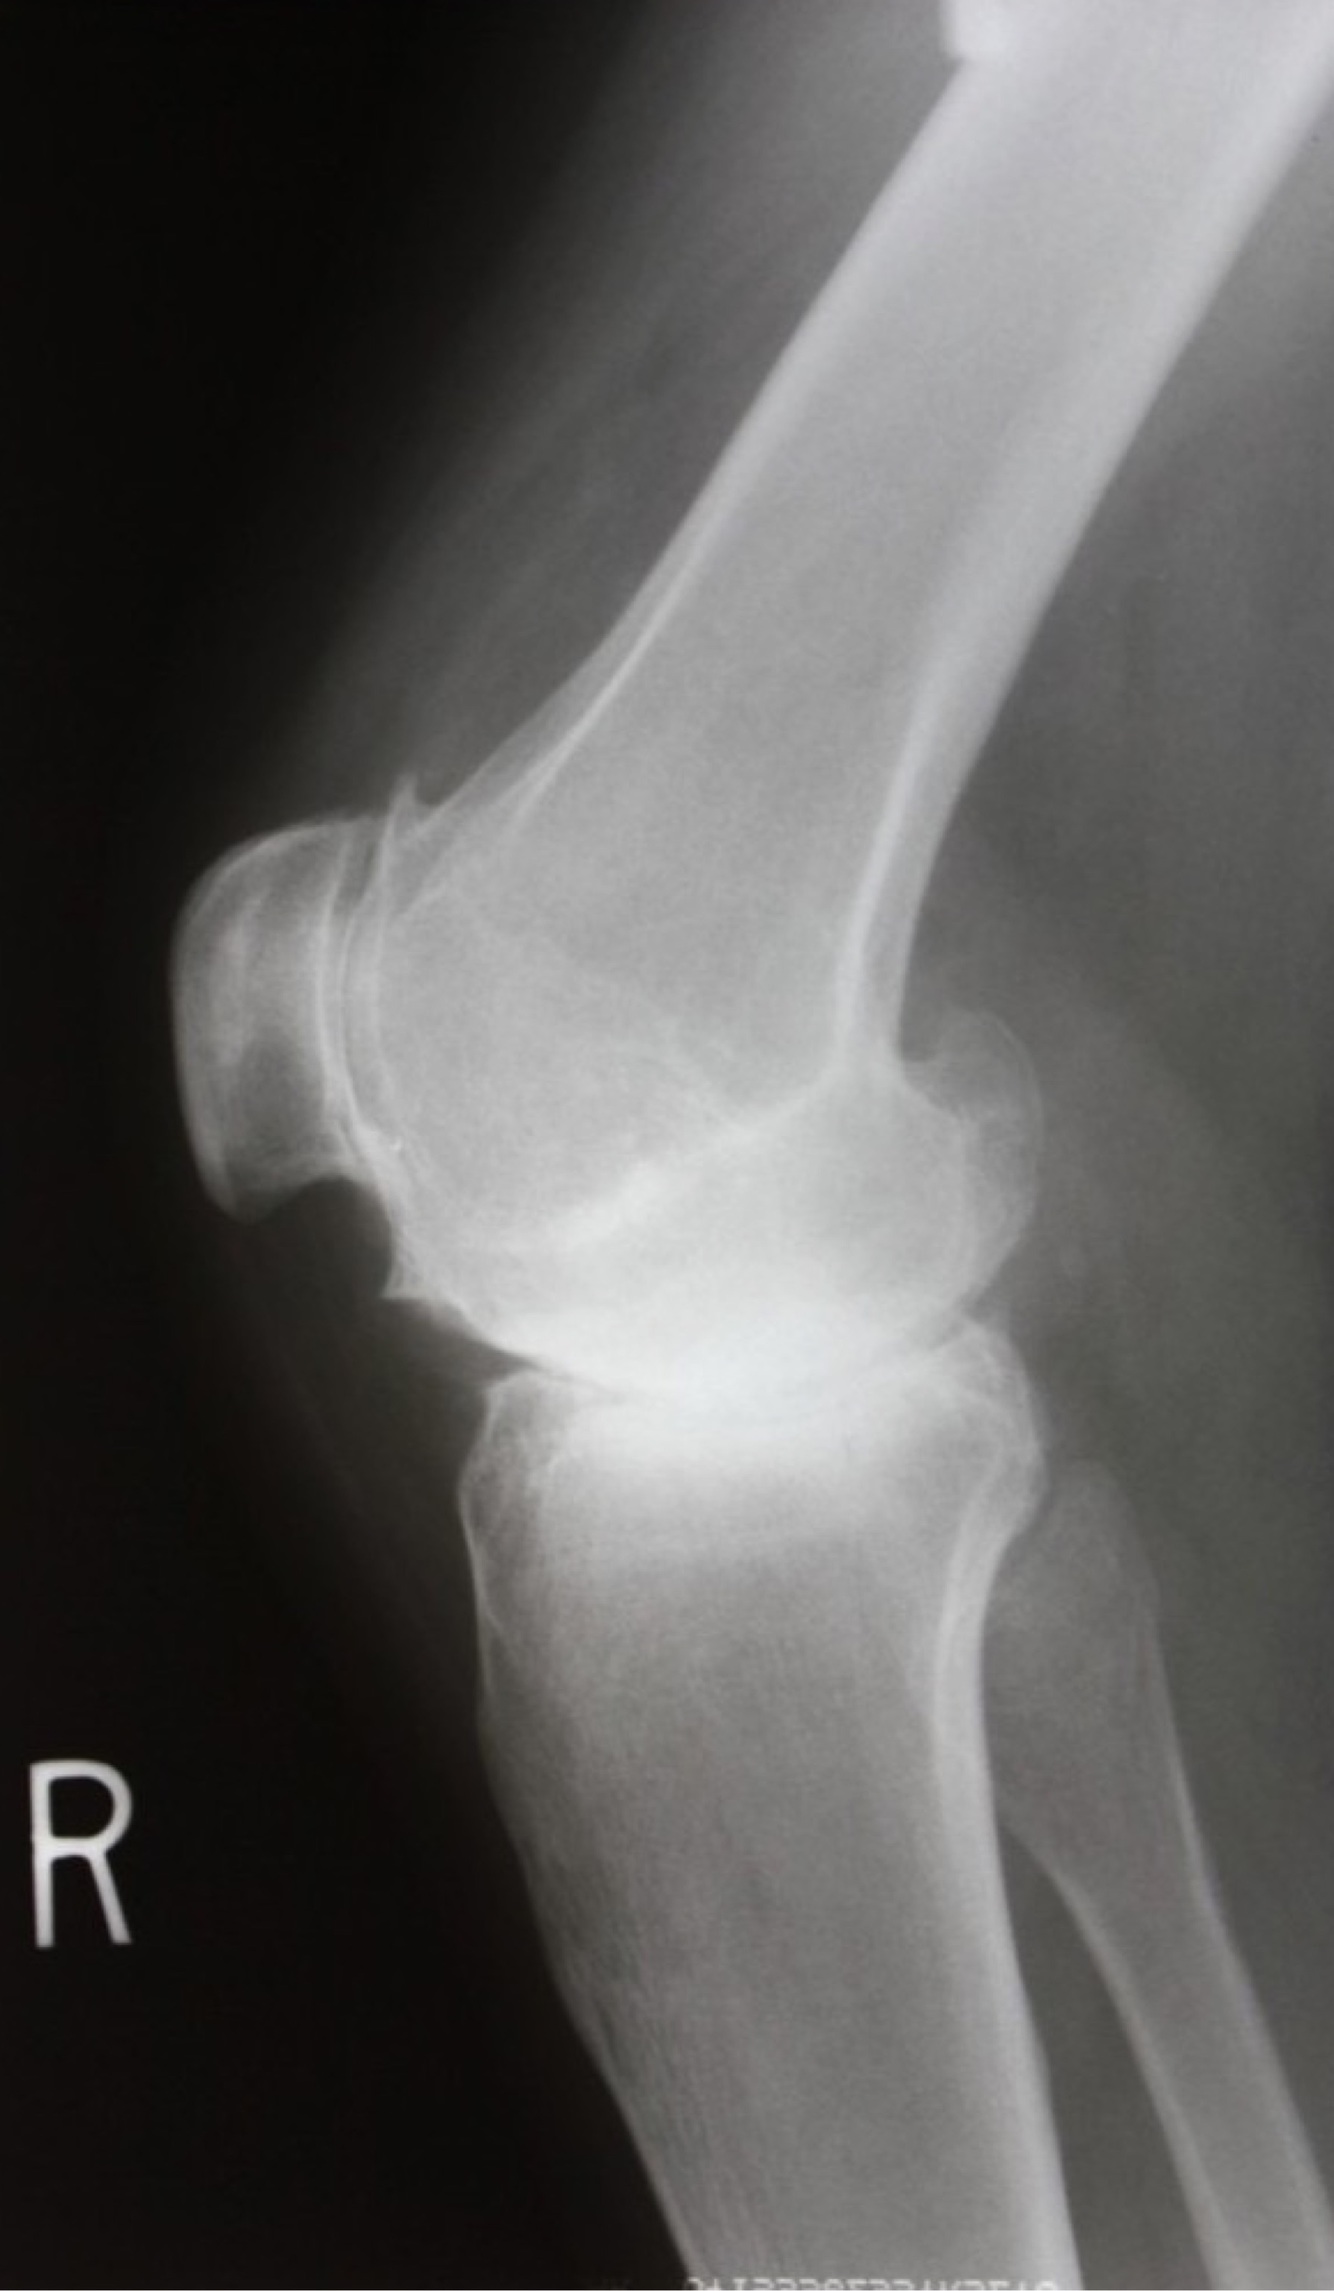

Q

Dx?

A

How well did you know this?